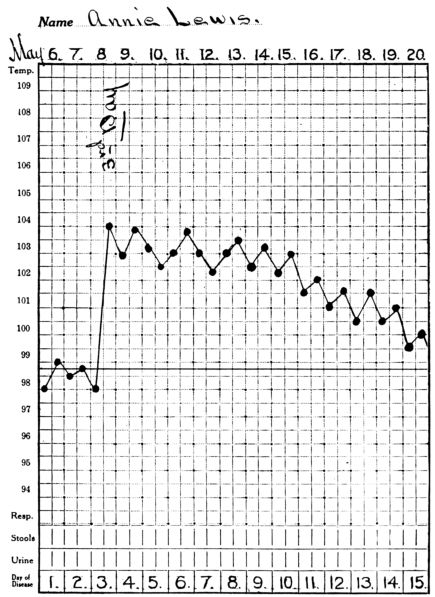

| 3. | Showing temperature curve in streptococcus infection | 397 |

| 4. | Showing temperature curve in gonorrhœal infection | 398 |